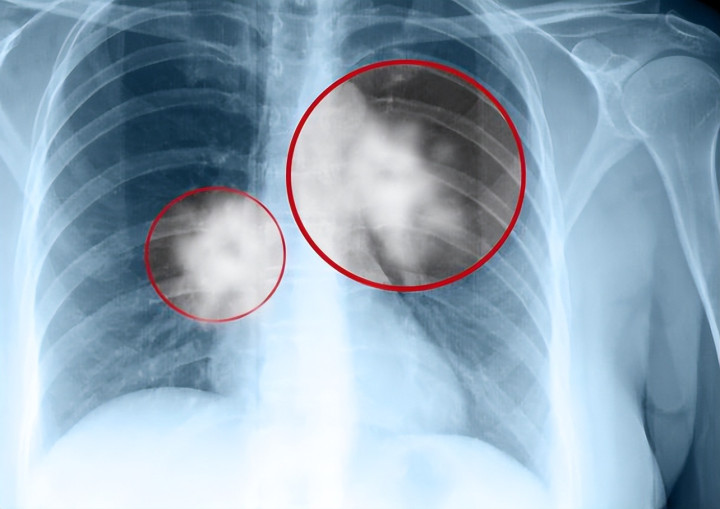

定期筛查是发现早期肺癌的有效途径。目前,低剂量螺旋CT被证实可显著提高早期发现率,降低死亡风险。对于40岁以上、有吸烟史或家族史的人群,每年一次筛查尤为重要。

肺癌真的会在一夜之间出现吗?许多人习惯性地认为,身体平时没有任何不适,突然检查就发现晚期肺癌,这似乎让人感到不可思议。然而,临床经验和大量研究都在提醒:肺癌并非骤然来袭,而是一个长期累积的结果。

肺癌的发生,往往经历了从细胞异常增殖到病理改变的漫长过程。忽视早期信号,才是导致确诊时已到晚期的真正原因。